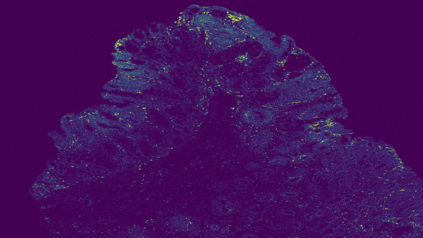

The usage of chemical imaging technologies is becoming a routine accompaniment to traditional methods in pathology. Significant technological advances have developed these next generation techniques to provide rich, spatially resolved, multidimensional chemical images. The rise of digital pathology has significantly enhanced the synergy of these imaging modalities with optical microscopy and immunohistochemistry, enhancing our understanding of the biological mechanisms and progression of diseases. Techniques such as imaging mass cytometry provide labelled multidimensional (multiplex) images of specific components used in conjunction with digital pathology techniques. These powerful techniques generate a wealth of high dimensional data that create significant challenges in data analysis. Unsupervised methods such as clustering are an attractive way to analyse these data, however, they require the selection of parameters such as the number of clusters. Here we propose a methodology to estimate the number of clusters in an automatic data-driven manner using a deep sparse autoencoder to embed the data into a lower dimensional space. We compute the density of regions in the embedded space, the majority of which are empty, enabling the high density regions to be detected as outliers and provide an estimate for the number of clusters. This framework provides a fully unsupervised and data-driven method to analyse multidimensional data. In this work we demonstrate our method using 45 multiplex imaging mass cytometry datasets. Moreover, our model is trained using only one of the datasets and the learned embedding is applied to the remaining 44 images providing an efficient process for data analysis. Finally, we demonstrate the high computational efficiency of our method which is two orders of magnitude faster than estimating via computing the sum squared distances as a function of cluster number.